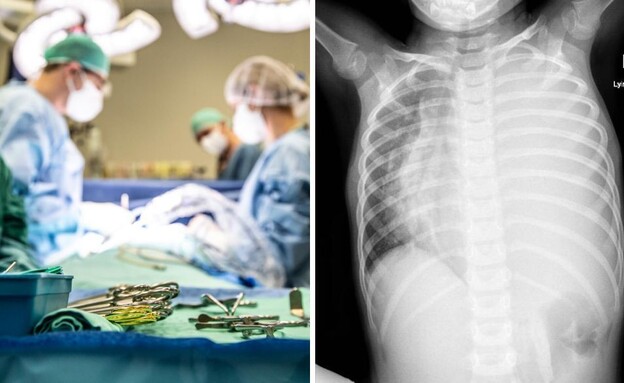

בגלל דלקת אוזניים: ילדים עברו כריתה של הלסת מיכל הלפרין | 21.12.25

טרגדיה בצפון: ילד כבן 4 נפטר משפעת יונתן דושניצקי | 19.12.25

"בכל שבוע נפטר ילד בריא ללא מחלות רקע" יונתן דושניצקי | 23.12.25

טרגדיה נוספת: ילד כבן 6 נפטר לאחר שסבל מחום יונתן דושניצקי | 22.12.25